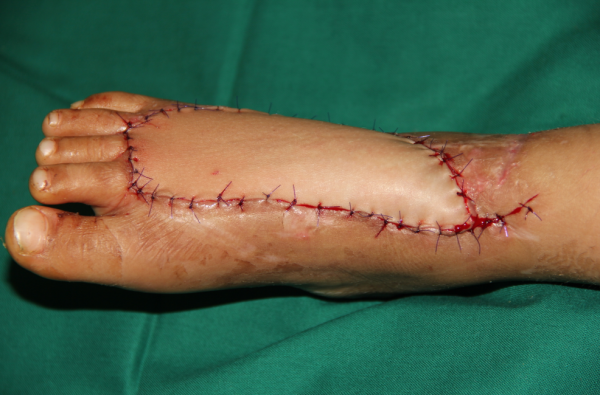

昨天做的腓骨皮瓣修复足部复合组织缺损,重建外侧负重及足横弓

也是玉米机伤。

解剖还算清楚,进修同道都看的很清楚

安装,修正骨头是最麻烦的,耗时间也最多

QQ截图20161016194130.png QQ截图20161016194151.png

搭建轮廓

QQ截图20161016194221.png QQ截图20161016194317.png

术后即刻

QQ截图20161016194237.png